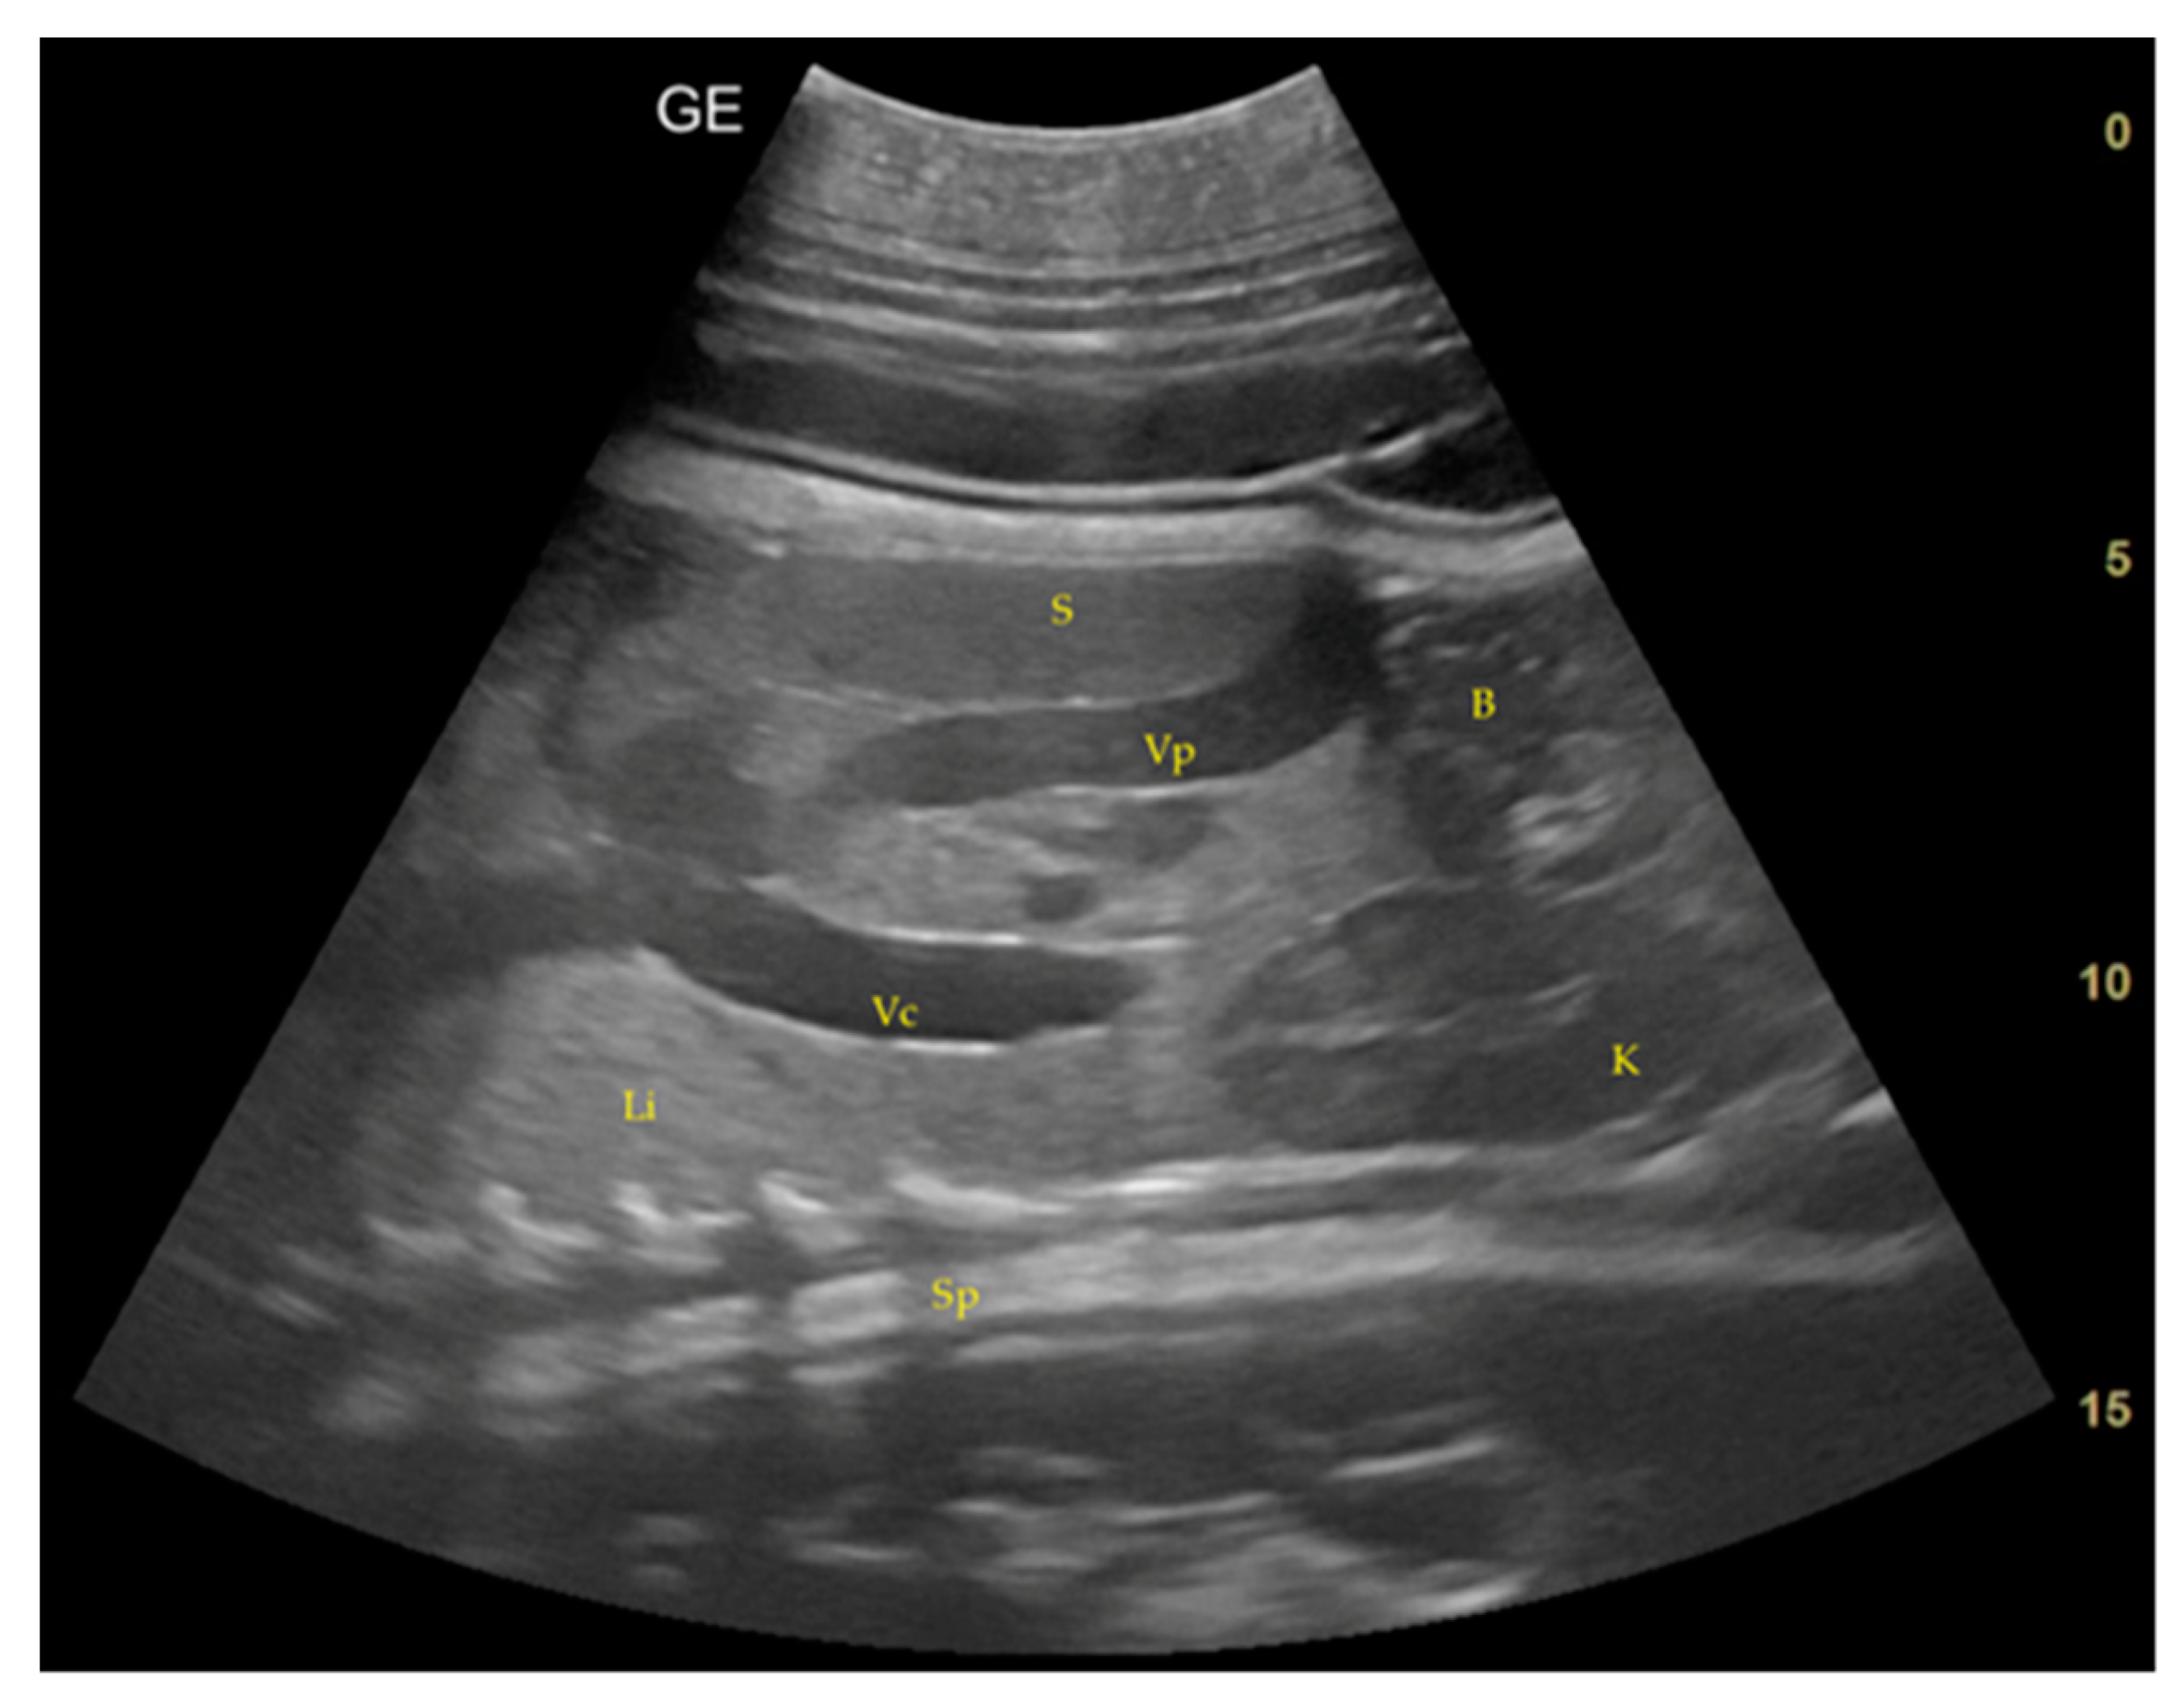

- Day 186 ± 2: It is possible to identify the heart, lungs in the thorax, diaphragm in the middle, and liver and stomach in the abdomen. (D) Lungs appear as hyperechoic structures on the sides of the heart, and the latter seems to have a similar echogenicity compared to the liver (Figure 4).

- Day 219 ± 3 days: It is also possible to recognize the eye as an anechoic cavitary structure (Figure 6). During the last month of pregnancy, it is possible to easily identify most of the abdominal organs such as the liver, spleen, intestine, and kidneys (Figure 7). In addition, the genitalia are visible and it could be possible to establish the sex of the fetus: in males, it is possible to identify the penis bone, which is obviously absent in females, but its visualization depends strongly on fetal position.